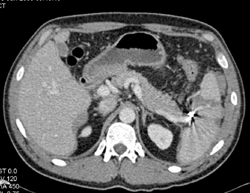

Pelvic Fractures